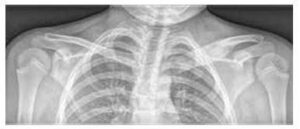

Este cea mai frecventă formă de cancer generalizat la adolescenți. Simptomele musculo-scheletale (MSK) sunt mai puțin frecvente decât în cazul ALL. Poate apărea durere osoasă (invazie a limfomului în cortex și măduvă, osteoartropatie hipertrofică care duce la periostită acută dureroasă), dar mai rar artrită. În diagnosticul diferențial al limfomului, este necesar să se excludă JIA sistemică, limfomul osos rar și osteomielita cronică. Pentru diagnostic, este necesară vizualizarea toracelui/mediastinului (RTG/CT), abdomenului (sono/CT) și examinarea histologică a ganglionilor (mai bine extirparea întregului ganglion decât biopsia).